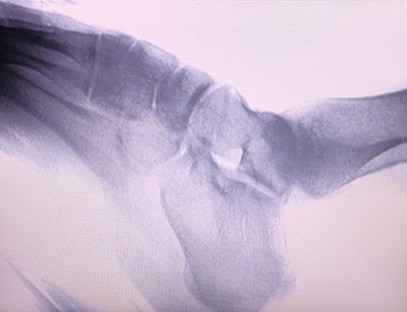

Das tragbare Röntgengerät As-c200 ist ein tragbares Instrument mit geringer Strahlendosis und sehr sicher. Es eignet sich besonders für Einheiten und Einzelpersonen mit unzureichendem Budget und geringen Anforderungen an Bilder. Die neue Generation ist mit einem 10-Zoll-HD-Großbildschirm ausgestattet, der einen größeren Perspektivbereich bietet und die gesamte Handfläche vollständig perspektivisch betrachten kann. Es ist vor allem aus medizinisch-orthopädischer Sicht geeignet. Es kann an einen Foliendrucker angeschlossen werden, um orthopädische Folien zu bedrucken, und kann auch in der industriellen Produktion und Prüfung eingesetzt werden. Keine Dunkelkammer, direkte Perspektive, sofortige Beobachtung, hohe Auflösung und klare Bildgebung.

Bei unserem orthopädischen Röntgengerät handelt es sich um ein hochwertiges Produkt, das speziell für die orthopädische Bildgebung entwickelt wurde. Es kann zur Diagnose und Behandlungsplanung verschiedener orthopädischer Erkrankungen verwendet werden, darunter Frakturen, Luxationen, Arthritis und Knochentumoren. Es ist mit fortschrittlicher Röntgentechnologie ausgestattet, die qualitativ hochwertige Bilder bei reduzierter Strahlenbelastung ermöglicht. Das Gerät verfügt über ein hochauflösendes Bildgebungssystem und kann Bilder jeder Knochenstruktur mit großer Klarheit aufnehmen.

Unser orthopädisches Röntgengerät kann in verschiedenen medizinischen Fachgebieten eingesetzt werden, darunter Orthopädie, Neurologie und Notfallmedizin. Es wird häufig zur fluoroskopischen Beobachtung menschlicher Gliedmaßenknochen, in Veterinär- und Tierkliniken sowie zur Behandlung von Verwundeten an Sportstätten, in Gebäuden, auf Hochseeschiffen, in abgelegenen Gebieten und auf Militärgeländen eingesetzt. Zu den klinischen Anwendungen gehören:

1. Diagnose von Frakturen, Luxationen und anderen Knochenverletzungen.

2. Beurteilung von Gelenkerkrankungen wie Arthritis, degenerativen Gelenkerkrankungen und Osteoporose.